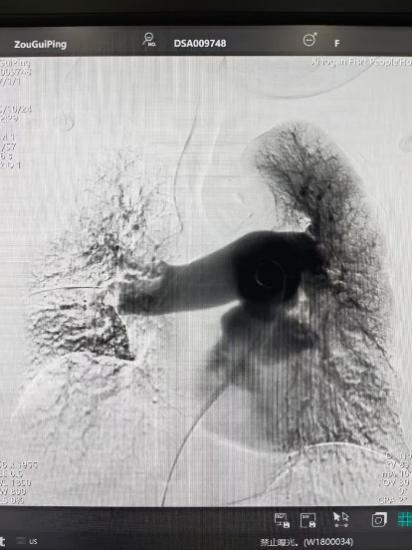

術(shù)后

手術(shù)在局部麻醉下進行,團隊通過股靜脈穿刺,將專用抽栓導(dǎo)管精準送達肺動脈栓塞部位,利用負壓抽吸技術(shù)成功清除大量血栓;隨后,在血栓局部精準灌注溶栓藥物,進一步溶解殘余血栓,恢復(fù)肺部血流灌注;同時,為防止下肢深靜脈血栓再次脫落引發(fā)肺栓塞,團隊為患者置入下腔靜脈濾器,整個手術(shù)歷時約1小時。術(shù)后,鄒婆婆呼吸困難癥狀即刻得到緩解,血氧飽和度顯著提升,右心負荷明顯減輕,目前身體狀況正在逐步恢復(fù)中。